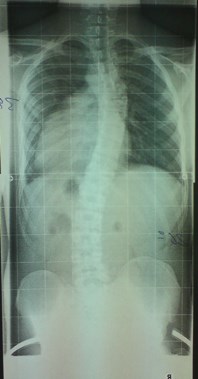

Das Röntgenbild vom November 2011 ist etwa 6 Wochen nach der Kur in Bad Salzungen geschossen worden. Mit 26° thorakal war das mein bester Wert, den ich je hatte. Leider bin ich dann wieder auf das Anfangsniveau von 34° thorakal zurück gefallen, trotz Korsett von cctec und ca. 120 Minuten Schroth-KG pro Woche. Ich muss dazu noch sagen, dass ich von Oktober 2010 bis November 2011 ein Korsett von Rahmouni getragen habe, allerdings nur etwa 8 Stunden am Tag, und die auch nicht am Stück. Das Korsett von cctec habe ich im Schnitt auch nur 8-10 Stunden pro Tag getragen. Aus privaten Gründen trage ich es seit Dezember 2013 nur noch sehr unregelmäßig, manchmal 3 Tage am Stück gar nicht, dann wieder 8 Stunden.

Mein Ziel war es immer gewesen, sowohl den Cobb-Winkel zu reduzieren als auch meinen Rücken zu symmetrisieren. Ersteres hat nicht geklappt. Und das zweite Ziel auch nicht wirklich. Der thorakale Skoliometer-Wert mag ein wenig geringer geworden sein, und die Hautfalte an der schwachen Stelle etwas unscheinbarer, aber ich bin immer noch krumm. Und ich fürchte, dass sich das mit konservativen Behandlungen bei mir auch nicht ändern wird. Immerhin sind Dr. Wilke und Herr Nahr mit meinem Rücken zufrieden.